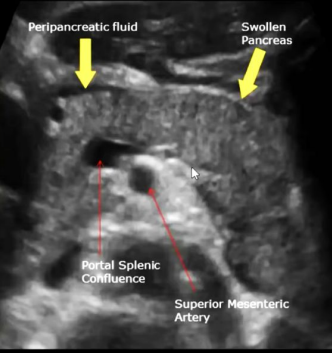

Transverse view of the pancreas

Pancreas appears to be swollen/enlarged with increased echogenicity and has peripancreatic fluid

Dx: acute pancreatitis